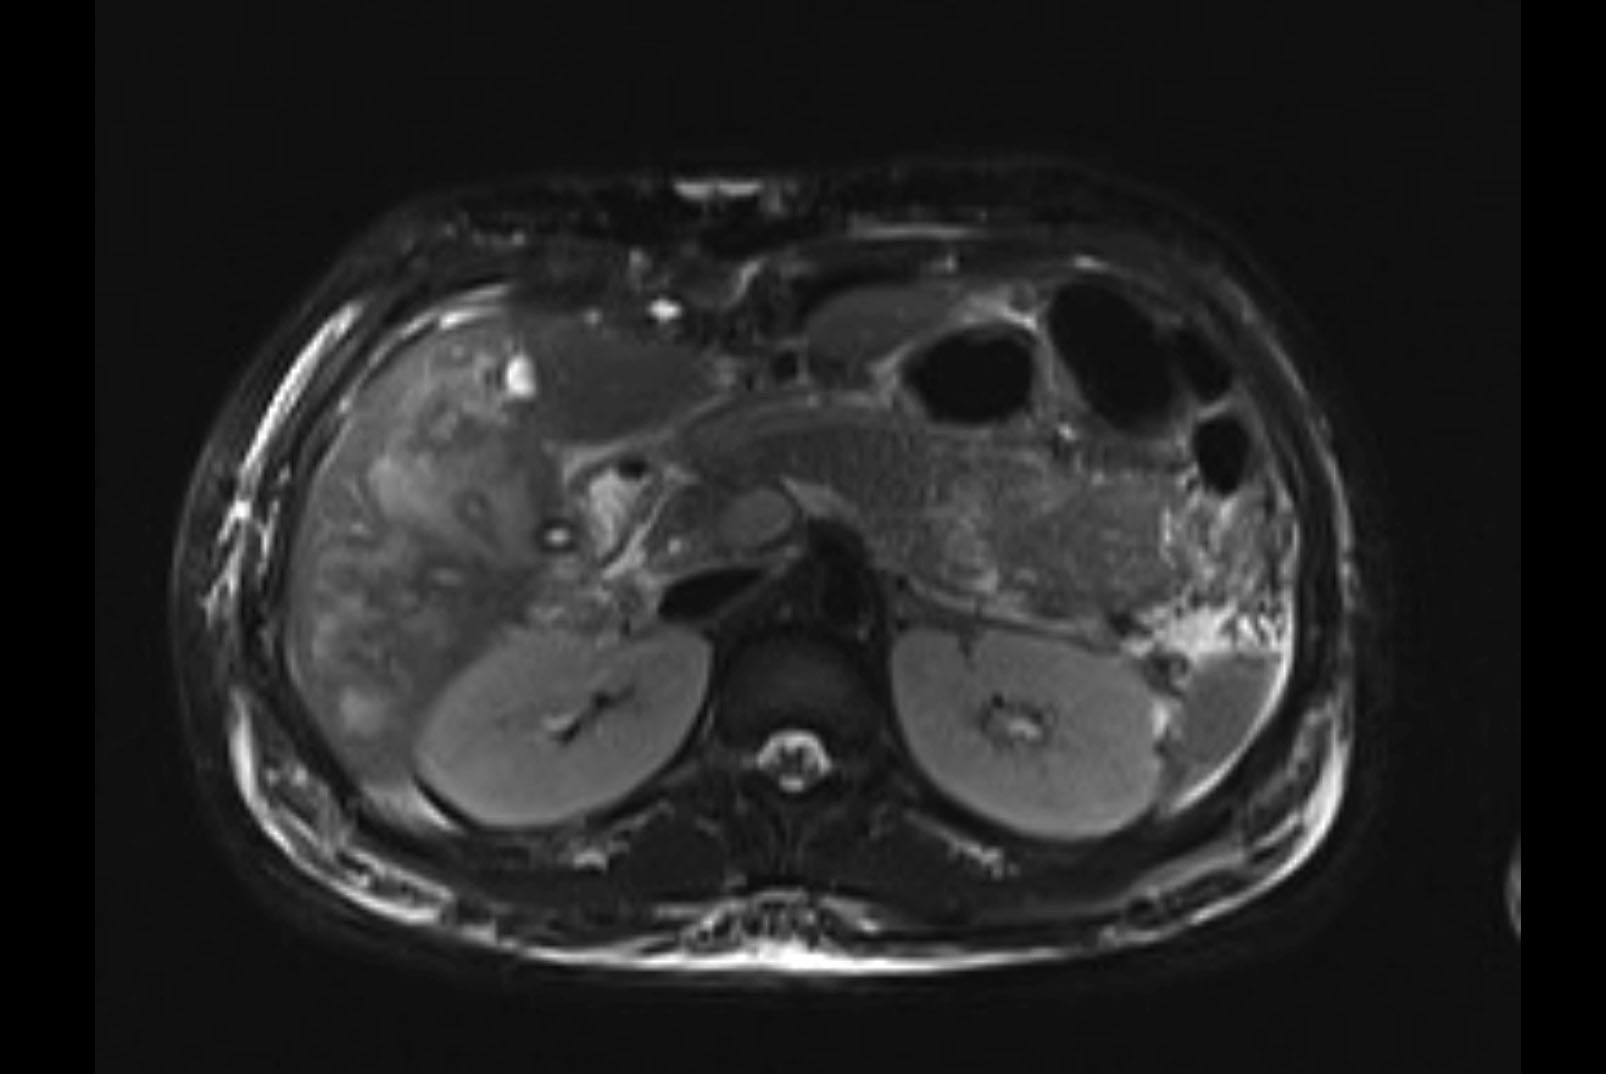

MRI T1

MRI T2